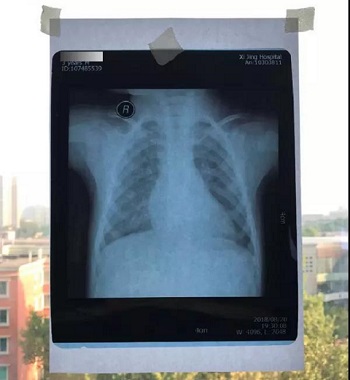

七、将白纸或白布贴于窗户玻璃上,然后将X光片或磁共振或CT片子贴于白纸或白布上。如果用的是电脑显示器翻拍片子,则按照上一条方法将显示屏变白色后,将片子贴于显示器上进行拍照。拍照时一定要正对着片子拍,注意横平竖直,拍端正了,不要拍歪斜了。

拍摄时,必须要对着片子上的文字对焦, 方向正确,将文字拍摄得清晰可视,保证放大图片后文字依然清晰可见(如下图),尽可能多的保留片子上的信息。